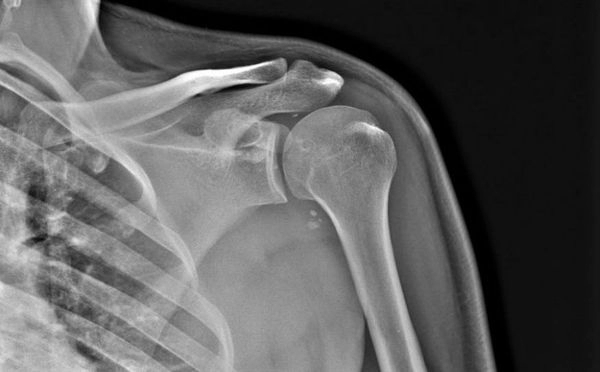

Рентген плечевого сустава

Наиболее доступный и информативный способ диагностики дисфункции плечевого сустава – рентгенография, т. е. исследование, выполняемое при помощи просвечивания больного плеча рентгеновским излучением.

В результате врач-рентгенолог получает серию изображений, которые в достаточно полном объеме раскрывают изменения в строении костных и хрящевых тканей, суставной сумки и прилегающих мягких тканей.

На основании снимков лечащий врач (травматолог, ортопед, хирург либо ревматолог) разрабатывает эффективную схему лечения пациента.

Рентгеновские снимки позволяют обнаруживать даже незначительные патологические изменения в костной и хрящевой ткани сустава: наличие воспалительного процесса, гноя, некротического поражения, деформации костей, скопления жидкости в суставной сумке и т. д. Наиболее явственно исследование показывает травматические повреждения костной ткани – переломы, трещин, наличие отломков кости. Помимо плечевого сустава, на снимке присутствует лопаточная кость и ключица, что обеспечивает комплексный подход к диагностике.